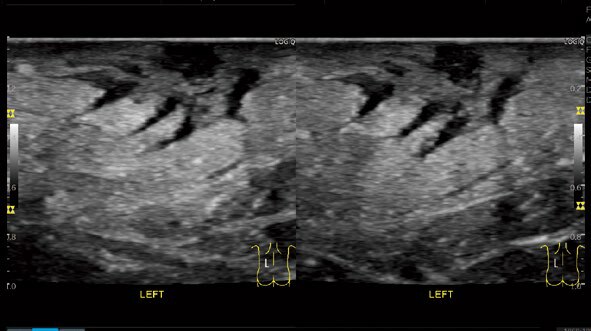

Shear Wave Elastography

シングルモードとマルチモードによる簡便な操作性を実現。

Quality Mapに基づいて精度の高い領域で計測でき、

様々な臓器に対し、組織の硬度を計測可能です。

Strain Elastography

歪みの程度をカラー表示。

クオリティを示すグラフとバーで高い再現性を担保できます。